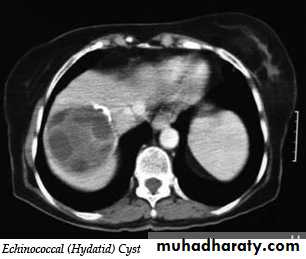

Hydatid cysts may be single or multiple; a few show calcified walls. Daughter cysts may be seen within a main cyst at both US and CT.